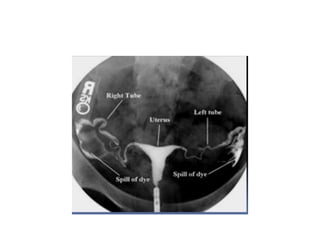

IMAGES should demonstrate

1) Full view of uterine cavity

2)Full view of fallopian tubes

3)Delayed view may be taken if there is

abnormal loculation of contrast

• Findings on HSG

• 1) Tubal blockages:

proximal/midsegmental/distal

IMAGES should demonstrate 1)Full view of uterine cavity 2)Full view of fallopian tubes 3)Delayed view may be taken if there is abnormal loculation of contrast After end of procedure- antibiotic course and inform vaginal spotting for 1-2 days

• Findings onHSG • 1) Tubal blockages: proximal/midsegmental/distal • 2)mullerian malformations • 3)Filling defects: submucosal fibroids,polyps, ashermans syndrome